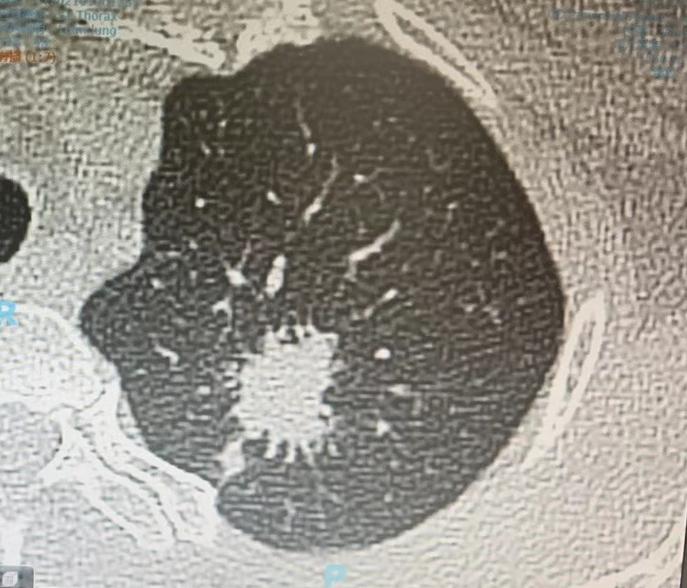

门诊来了一对夫妻,先生50岁上下,坐在那儿一声不吭,脸色沉沉的。他太太站在身后,一句接一句地跟我说他的情况,从语气上能听出十分的着急。 这场景我突然觉得特别熟悉——再仔细一看,才想起来这位先生两年前其实来找过我。 那时候他查出来肺上有个肿块,大家都以为是肺癌,连手术都准备安排了,就在术前,我多问了一句:“平时晚上睡觉,会不会出汗低热?” 他愣了一下,说确实经常睡到半夜一身湿透。 就这一句话,让我觉得不对劲。我建议他先别急着手术,去排查一下结核。结果出来,果然是肺结核——不用开刀,吃药就行。 那为什么两年后,他又来找我了呢? 他太太说,之前吃药后病灶确实小了,两年都挺平稳。可最近复查,报告上写着“肺结节,有毛刺,早期肺癌待排除”。两个人一看,顿时慌了神。 我把他这次的片子和两年前的对比了一下,心里就有数了。这个结节,在抗结核治疗后的头一年里,其实一直在慢慢缩小,直到最近这一年,已经完全稳定、没再变化了。 虽然报告上写着“毛刺”“恶性可能”,但时间已经给出了答案:这是个结核治好后留下的陈旧灶,说白了,就是肺上的一道“疤痕”。 我看着他和他太太,很肯定地告诉他们:“别担心,这个不是肿瘤,是良性的,定期复查就行”...... 他们俩的表情,一下子就松了下来。所以也想借这个事跟大家说,影像报告上的描述,不是绝对的“判决书”。有时候,时间才是最好的医生——它能告诉我们什么是真凶,什么是虚惊。[作揖][玫瑰]